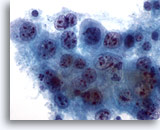

画像 4

肺FNA、肺腺癌

波状縁を呈する悪性腺細胞の集塊。背景には何も見られず、腫瘍性背景を呈していません。悪性細胞の保存状態は良好です。細胞質には、離散性の空胞が微細なものから大きなものまで見られ、一部には取り込まれている好中球が認められます。 60倍

画像 4

肺FNA、肺腺癌

波状縁を呈する悪性腺細胞の集塊。背景には何も見られず、腫瘍性背景を呈していません。悪性細胞の保存状態は良好です。細胞質には、離散性の空胞が微細なものから大きなものまで見られ、一部には取り込まれている好中球が認められます。

60倍